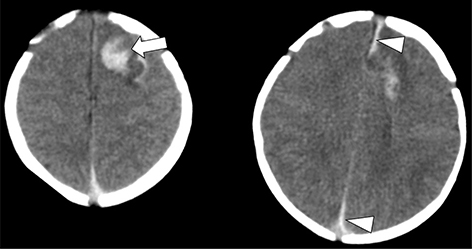

Acute phases of fetal stroke, such as in case of congenital heart disease or twin-twin transfusion syndrome (TTTS), may only rarely be detected prenatally. Fetal stroke often manifests with the chronic features of unilateral ventriculomegaly and volume loss with or without associated hemorrhage (Figures 1 and 2).

Fig 1

Figure 1. Acute and chronic fetal infarctions. 29 weeks of gestation fetus with a chronic stroke in the right hemisphere. (A) Axial HASTE (Half Fourier Singleshot Turbo Spin-Echo) and (B) Gradient Recall Echo (GRE) images showing unilateral enlargement of the right lateral ventricle, with periventricular white matter loss (white arrow) and linear blood staining (black arrowhead). 21 weeks of gestation fetus with congenital heart disease with acute stroke in the right hemisphere. (C) Axial DWI and (D) ADC map showing areas of reduced diffusion in the left ACA and MCA territories (black arrow) with questionable infarct in the right MCA territory (white arrowhead). Case courtesy of Dr. Tamara Feygin, Department of Radiology, Children’s Hospital of Philadelphia.